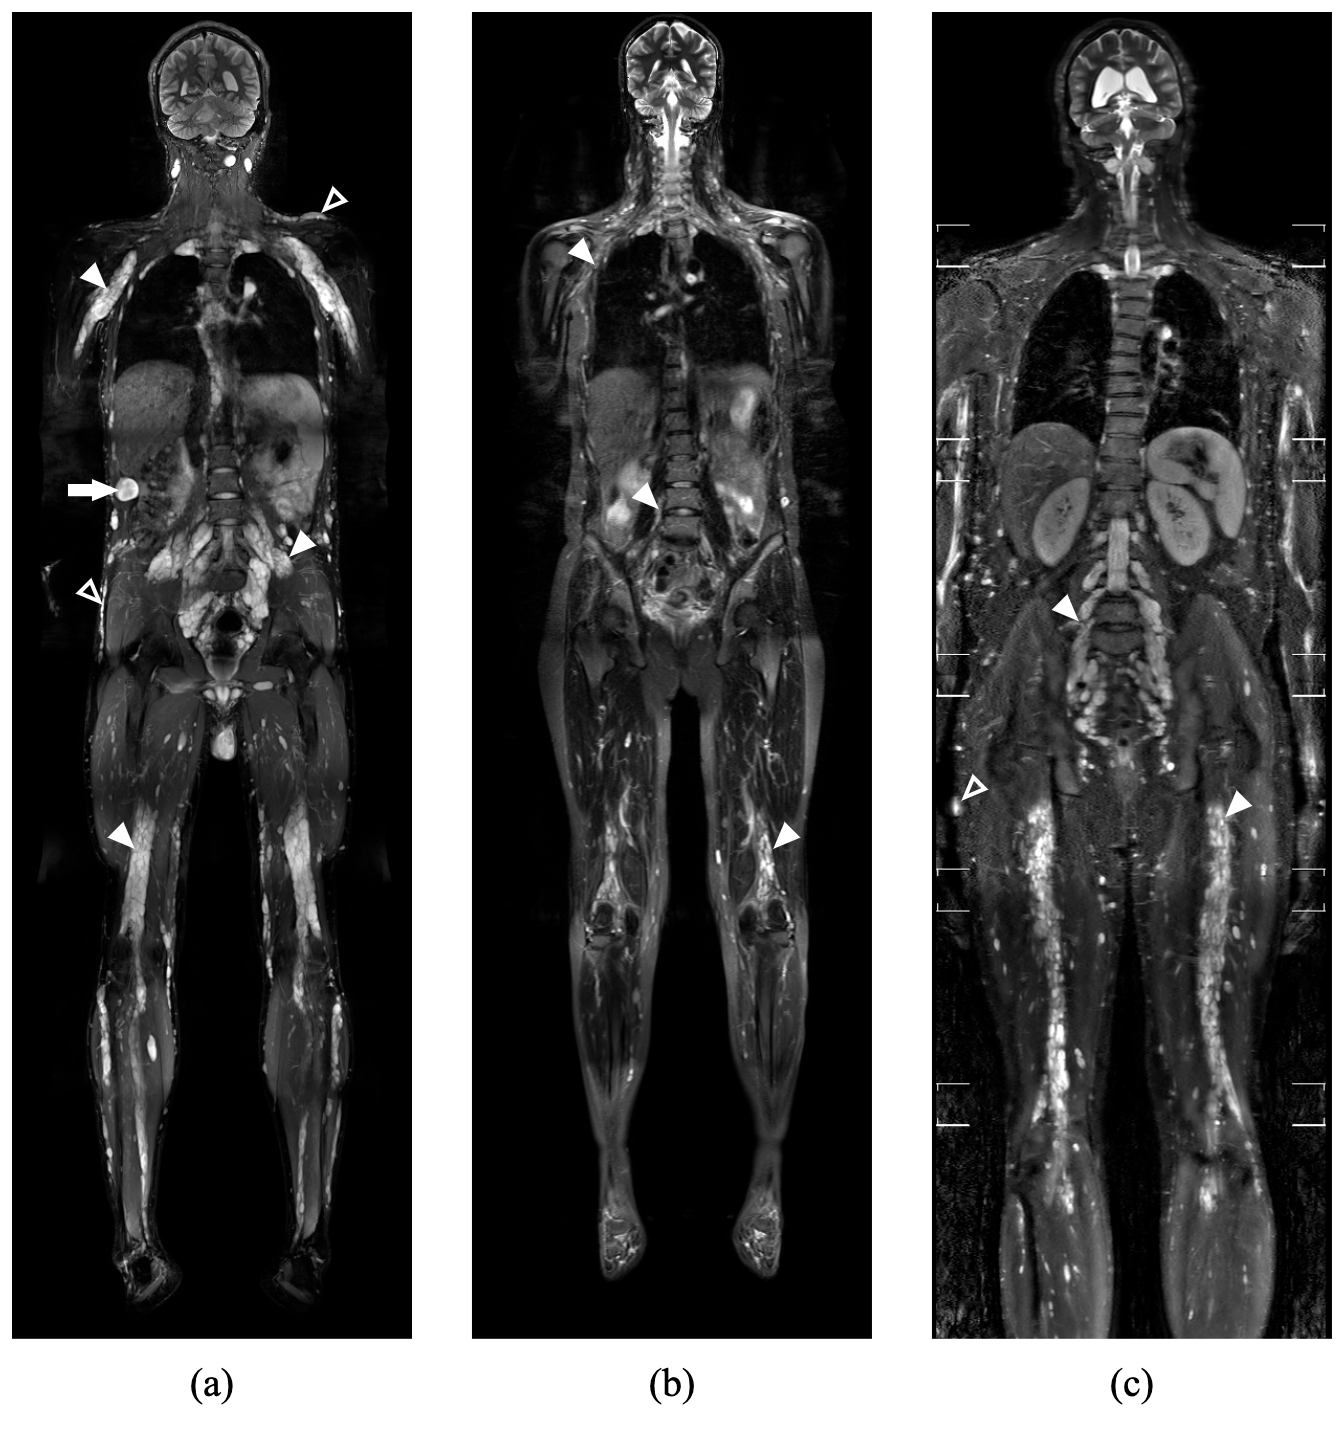

Figure 1: T2-weighted fat-suppressed whole-body MRI scans of three patients with neurofibromatosis type 1, illustrating variability in tumor burden and scanner characteristics. Highlighted examples include plexiform neurofibromas (filled arrowheads), subcutaneous neurofibromas (empty arrowheads), and distinct nodular lesions (filled arrows). (a) A male patient with a tumor burden of 6679 cm3, scanned using a 3T Siemens Magnetom scanner. (b) A female patient with a tumor burden of 1316 cm3, scanned using a 1.5T Siemens Magnetom scanner. (c) A male patient with a tumor burden of 2348 cm3, scanned using a 3T Philips Ingenia scanner.